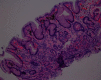

Gastric pseudomelanosis is a benign condition that has been characterized by pigment deposition within subepithelial macrophages inside the stomach wall. Occurrence of the condition is rare, with pseudomelanosis occurring more often within the duodenal mucosa. Few cases have reported pseudomelanosis within the gastric mucosa. We report a case of an 86-year-old female who presented with worsening iron deficiency anemia concerning for gastrointestinal bleeding. Her endoscopic evaluation was remarkable for a speckled pattern of dark pigmentation within the stomach, confirmed to be pseudomelanosis by histologic evaluation with pigment showing positive staining for iron.